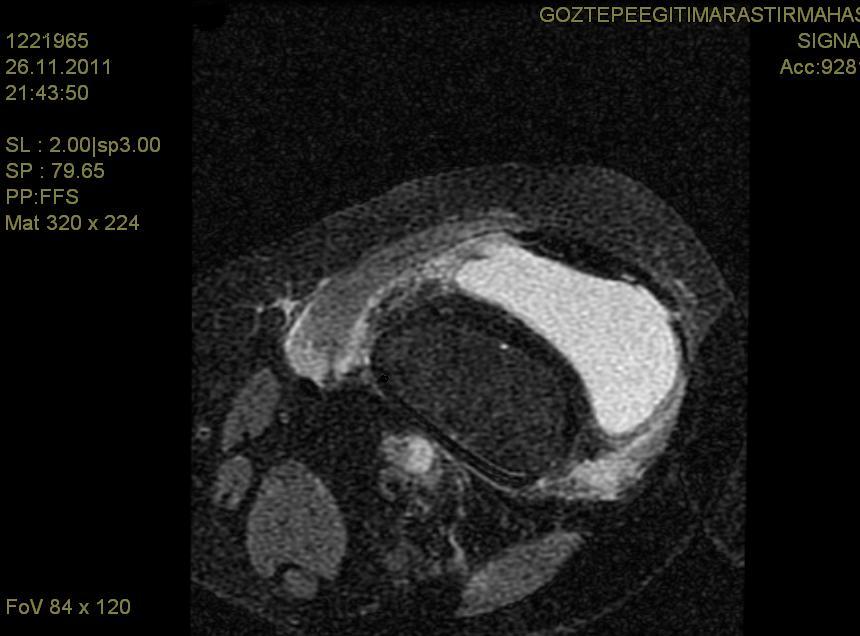

As a Rare Site of Invasive Fungal Infection, Chronic Granulomatous Aspergillus Synovitis: A Case Report